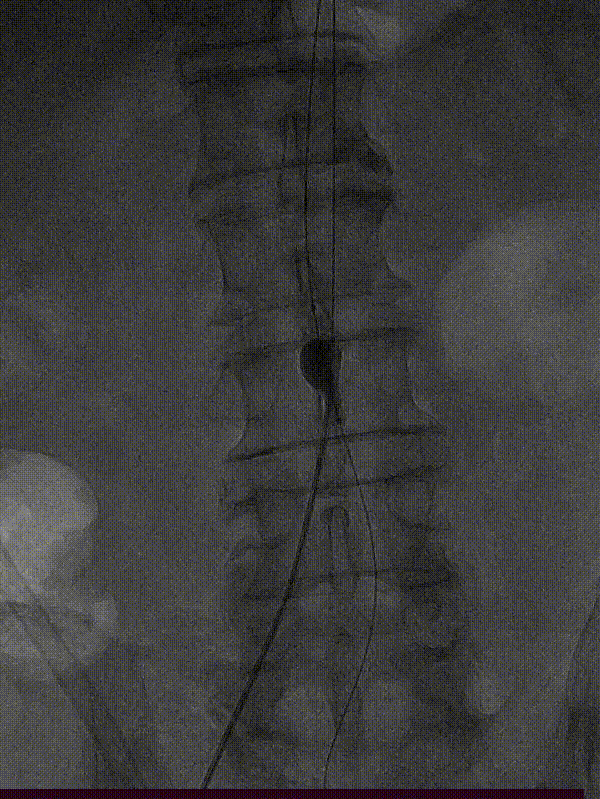

左侧肱动脉入路,主髂动脉造影

双侧股动脉切开,经股动脉7F Fogarty导管取栓